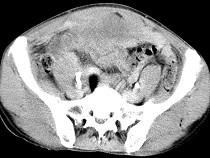

问题 男,56岁,无规律上腹痛,左锁骨上淋巴结肿大,消瘦、乏力,影像检查如图,最可能的诊断是 ( )

选项 A.腹膜结核 B.胃溃疡穿孔 C.胃癌并盆腔种植 D.胃及腹腔淋巴瘤 E.肠系膜淋巴管瘤

答案 C